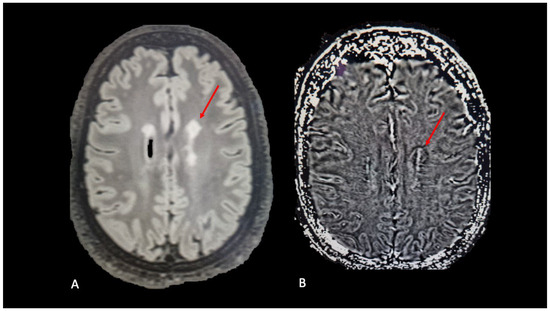

- Ruetten, P.P.R.; Gillard, J.H.; Graves, M.J. Introduction to Quantitative Susceptibility Mapping and Susceptibility Weighted Imaging. Br. J. Radiol. 2019, 92, 20181016. [Google Scholar] [CrossRef]

- Liu, C.; Li, W.; Tong, K.A.; Yeom, K.W.; Kuzminski, S. Susceptibility-weighted imaging and quantitative susceptibility mapping in the brain. J. Magn. Reson. Imaging 2015, 42, 23–41. [Google Scholar] [CrossRef] [PubMed]

- Kim, S.; Lee, E.K.; Song, C.J.; Sohn, E. Iron Rim Lesions as a Specific and Prognostic Biomarker of Multiple Sclerosis: 3T-Based Susceptibility-Weighted Imaging. Diagnostics 2023, 13, 1866. [Google Scholar] [CrossRef]